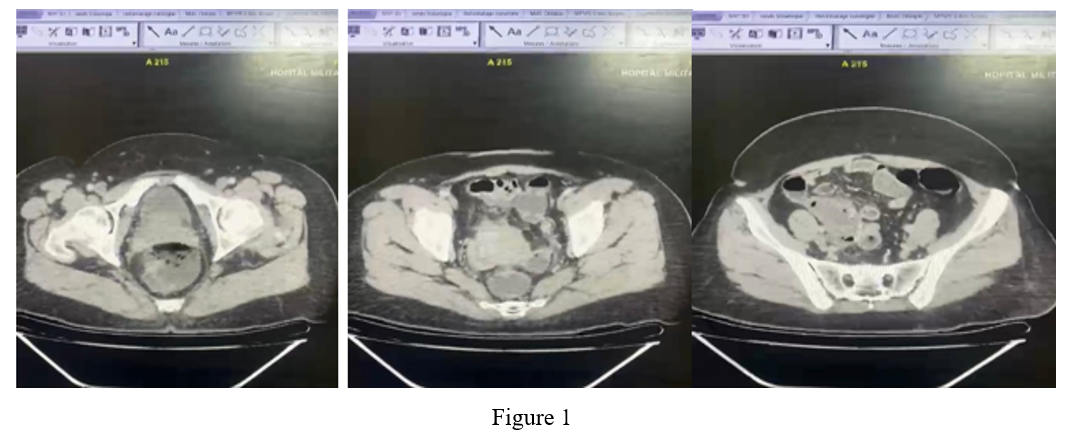

A 47-year-old patient with no particular medical history presented with hypogastric abdominal pain and fever of 40 degrees Celsius (104.4 Fahrenheit) for the past 48 hours. Physical examination noted guarding in the right iliac fossa and hypogastric region. Blood count: White blood cell count at 17,000 cells/mm3, predominantly polymorphonuclear neutrophils. Abdominal CT: Tubular formation at the level of the IDF measuring 34 mm in maximum thickness, with fluid content and a calcified wall enhanced after injection of contrast agent with a fluid collection around it.

Figure 1